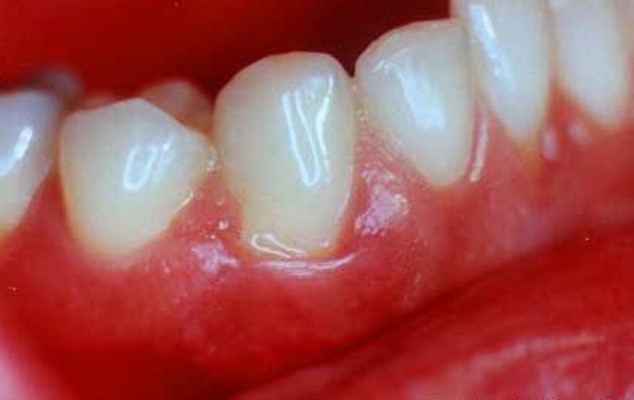

牙周炎圖片

牙周袋 (9)